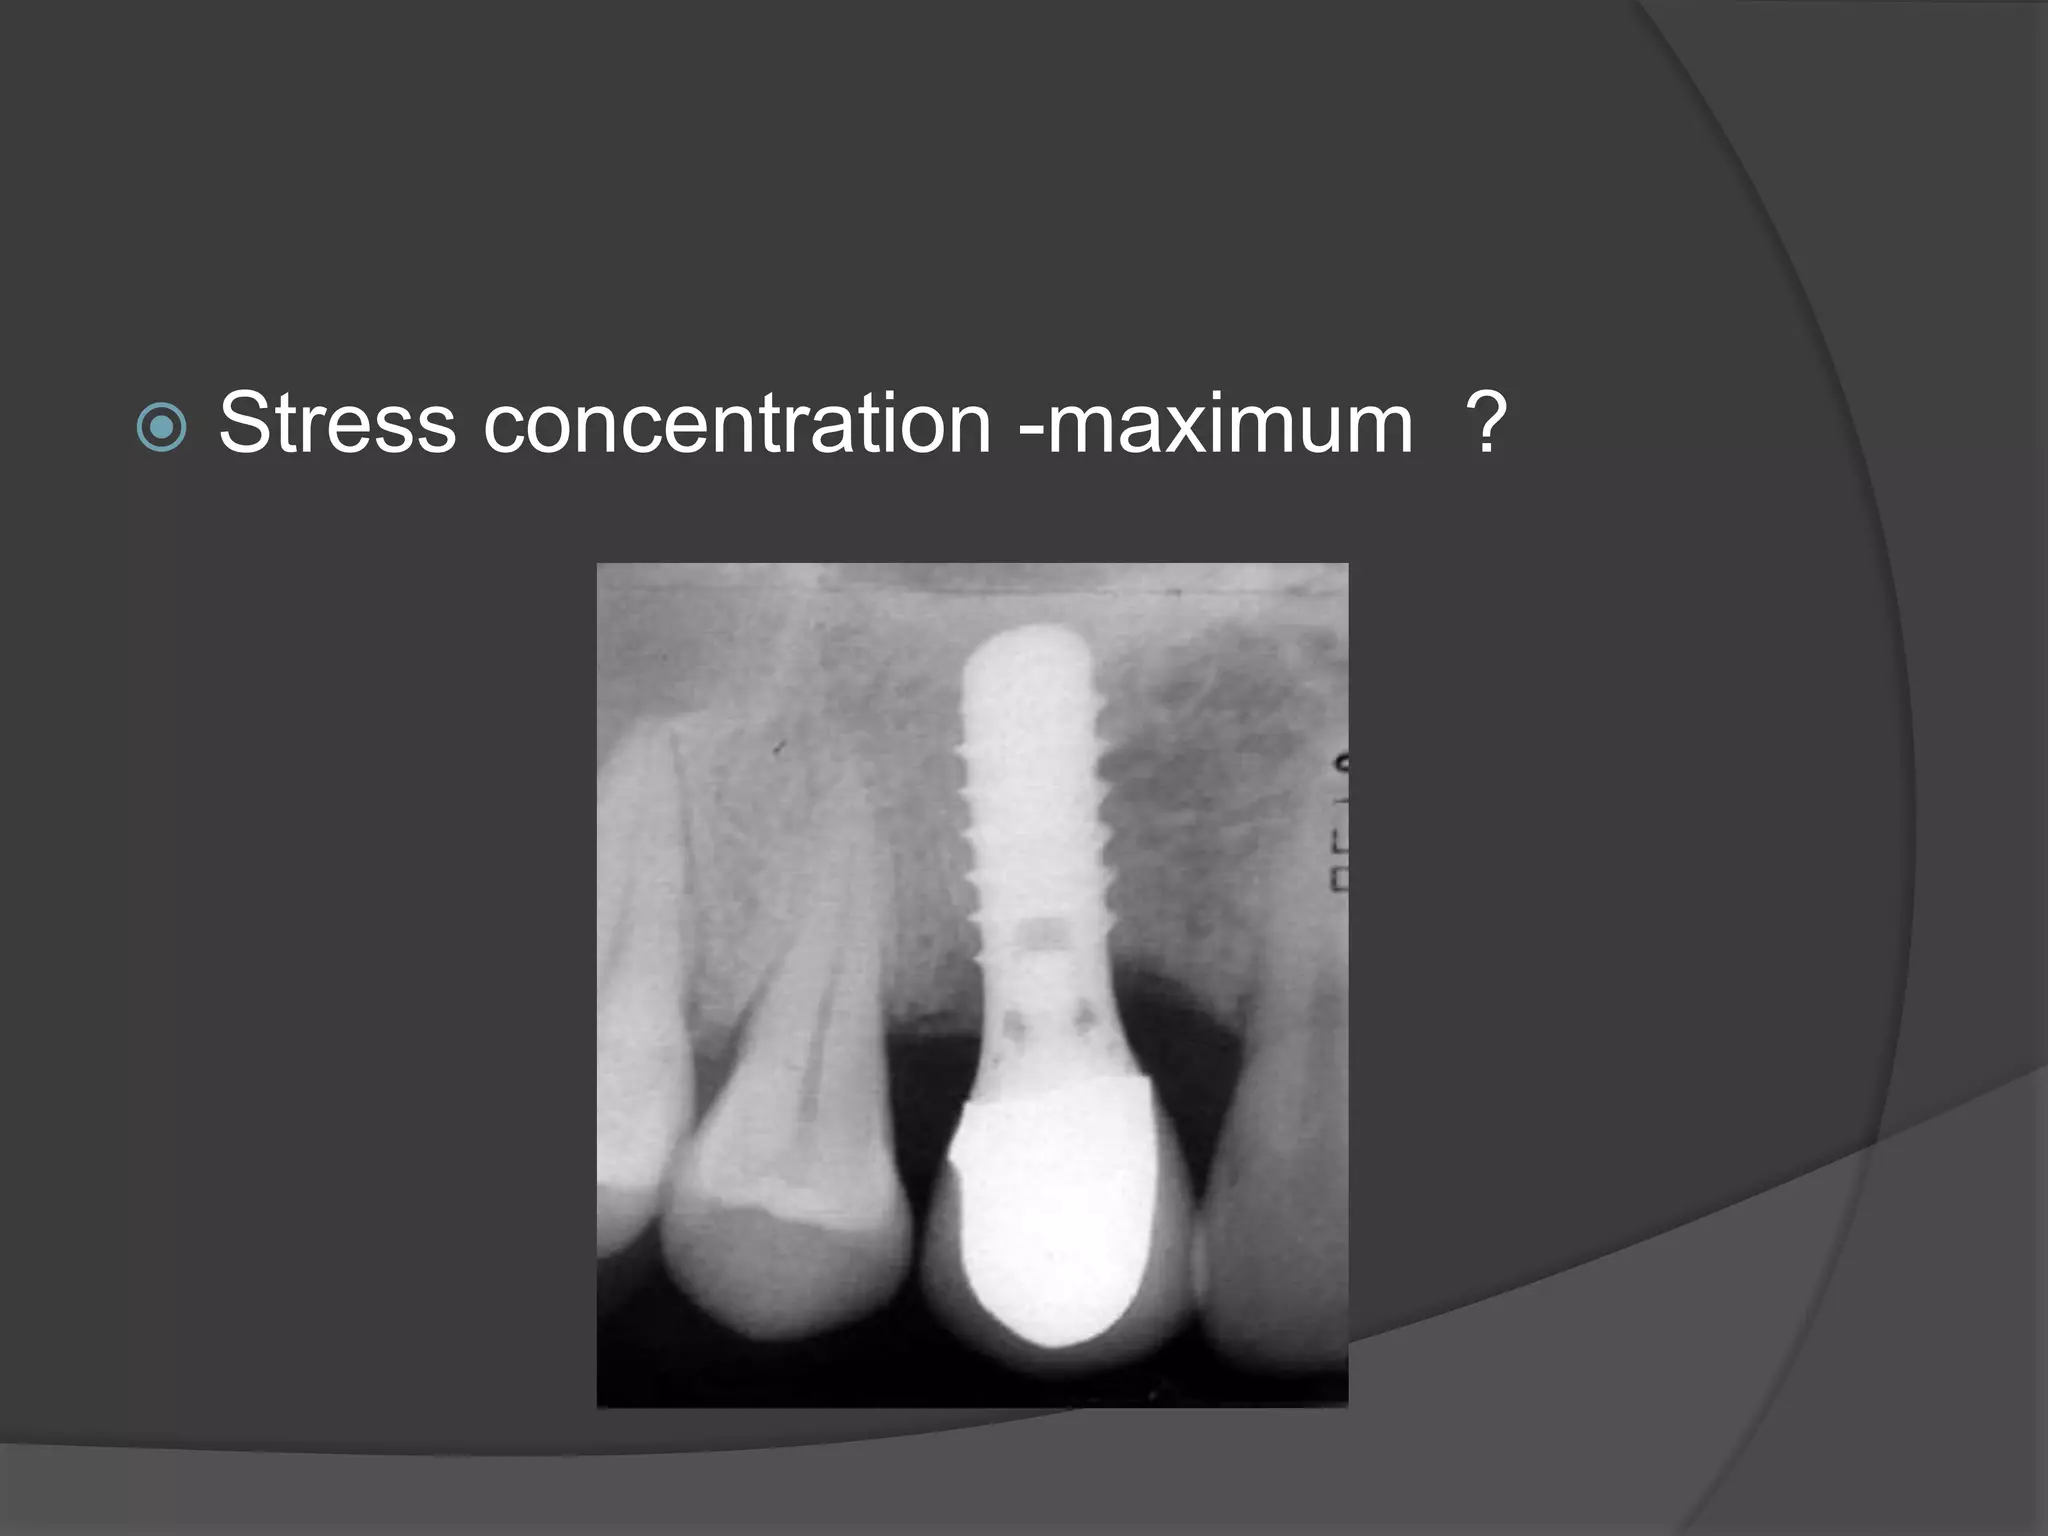

This document discusses factors that influence osseointegration and primary stability of dental implants, including implant design characteristics, surgical technique, and loading protocols. Specifically, it covers the processes of osseointegration and how forces on implants can either promote or inhibit bone remodeling. Key implant design considerations like length, diameter, threads, coatings and surface topography are analyzed in terms of their effects on stress distribution and bone-implant contact. The importance of primary stability and factors influencing it like bone quality and surgical skill are also addressed. Loading protocols ranging from immediate to conventional loading are compared.